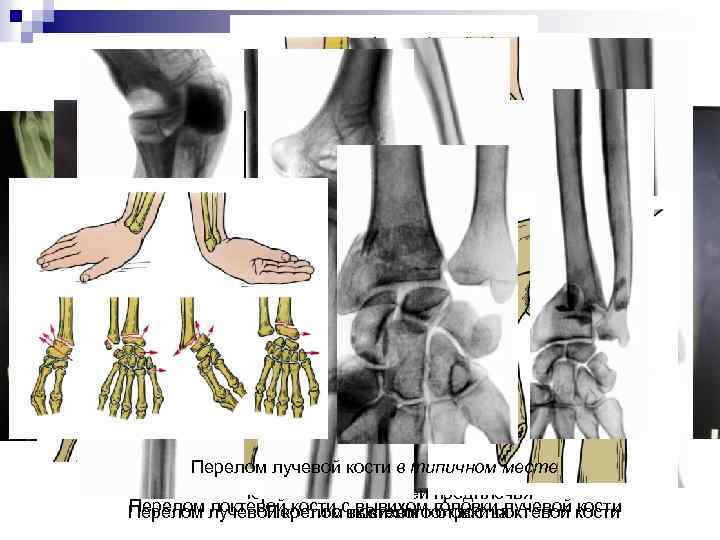

Переломы лучевой/локтевой костей n n n Ш Ш Ш Ш Ш Причины: прямой удар, резкая угловая деформация. Признаки: Деформация, отечность, нарушение движений, болезненность при пальпации области перелома, болезненность при нагрузке по оси предплечья, патологическая подвижность и крепитация на уровне перелома. При переломе одной из костей предплечья деформация и отечность выражены не так сильно, а локальная болезненность определяется только в области поврежденной кости. При рентгеновском исследовании обнаруживают линию перелома. Классификация Перелом локтевого отростка Перелом венечного отростка Перелом головки и шейки лучевой кости Изолированный перелом локтевой кости Изолированный перелом диафиза лучевой кости Перелом обеих костей предплечья Перелом локтевой кости с вывихом головки лучевой кости Перелом лучевой кости с вывихом головки локтевой кости Перелом лучевой кости в типичном месте.

Перелом лучевой перелом локтевой месте Изолированный кости в типичном кости Изолированный перелом диафиза лучевой кости Перелом обеих костей предплечья Перелом локтевой кости вывихом головки локтевой кости Перелом лучевой кости сслоктевого головки лучевой кости Перелом вывихом отростка